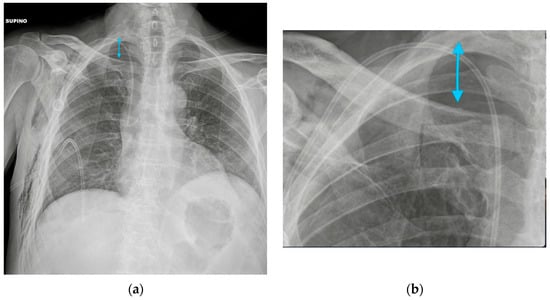

3.1. Central Vein Catheter (CVC)

3.2. Peripherally Inserted Central Catheter (PICC)